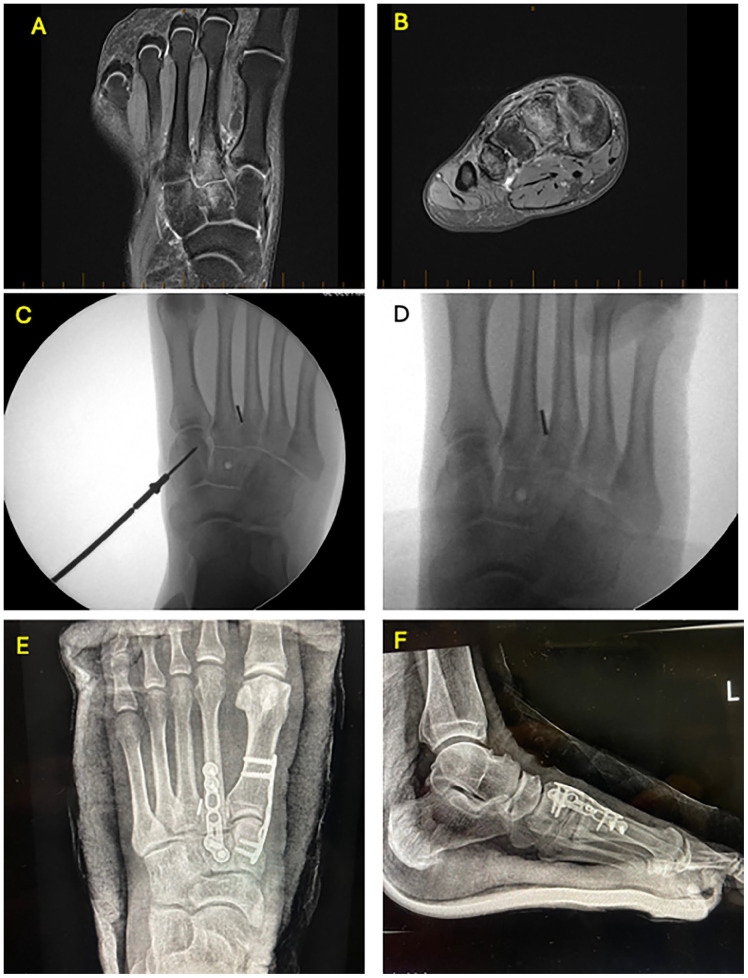

Abstract Image